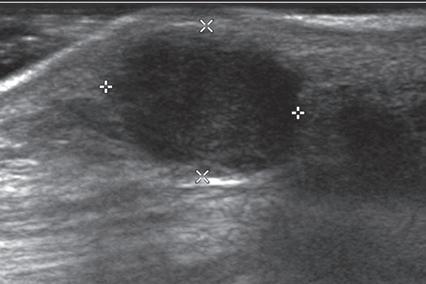

FIGURE 1.18 Increased Through-Transmission. Ultrasound image of a pigmented villonodular tenosynovitis (giant cell tumor of the tendon sheath) (between × and + cursors) shows increased through-transmission (open arrows).